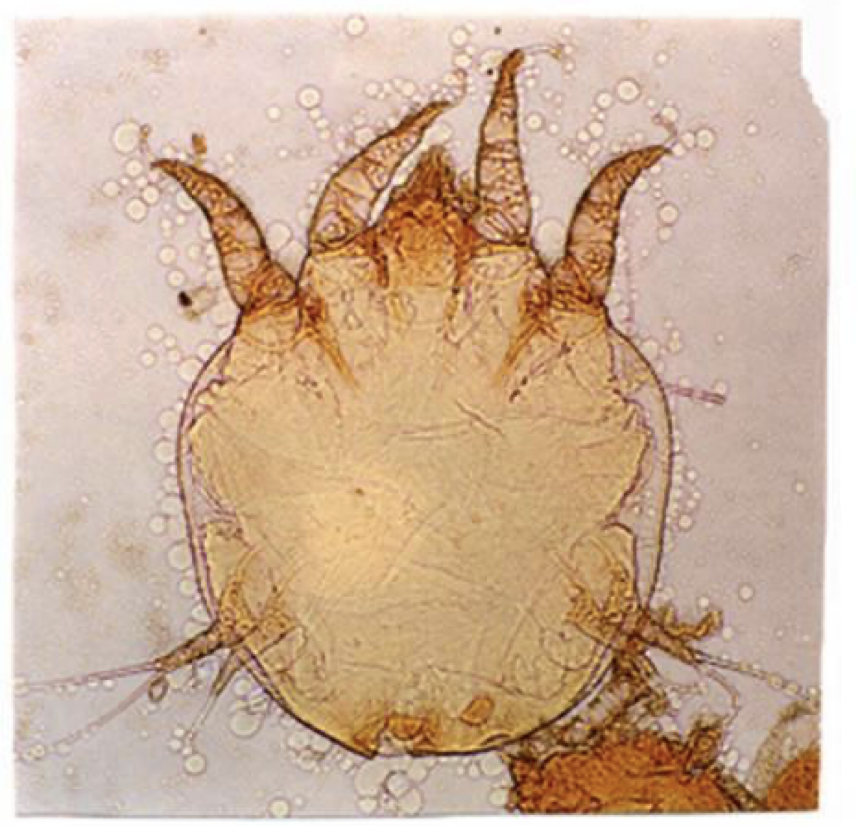

P.cuniculi

P. cuniculi

chorioptes equi